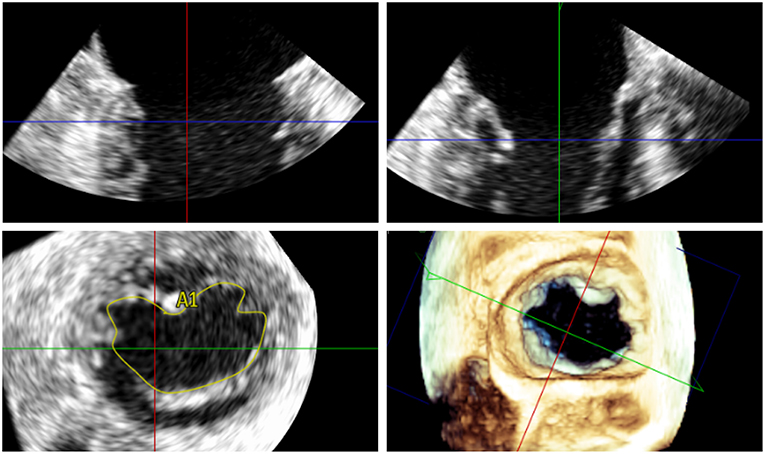

Newest Iteration: MitraClip XTR

There is currently a new version of the clip, the MitraClip XTR (MC XTR), which is similar to the first generation and NT versions of the MC in that it consists of a 24 French steerable guide catheter and a steerable clip delivery system (CDS). The MC XTR has a 5 mm longer clip grasping width due to longer arms (22 vs. 17 mm compared with the NTR). The transition zone between the delivery sheath and the CDS has been reinforced to improve stability during rotation of the CDS. The steerable sleeve is also more responsive to the rotation of the M-knob. The working length of the system has been increased by 1.5 cm and changes to the mechanism and material of the lock line enable operation of the system in the “unlocked” position. Finally a new Nitinol rather than Elgiloy gripper line enables a deeper gripper drop and grasping angle. Ultimately, the MC XTR may enable easier and quicker leaflet grasping, reduce the number of clips required and expand percutaneous treatment to patients with less favorable anatomy.

On the other hand, grasping more tissue may result in additional tension on the leaflets that concentrates at the tip of the clip arms. This may provoke leaflet damage, especially in patients with calcifications, fragile, or thin appearing leaflets. Moreover, due to the increased length of the clip arms, the risk of entrapment in the subvalvular apparatus is certainly higher, particularly when treating commissural lesions. According to a recently published multicenter experience in 107 patients treated with the MC XTR, procedural success was high with MR≤2+ in 93% of the patients and ≤1+ in 77%. However, four patients had leaflet damage requiring surgical correction during the same hospitalization (16). Thus, the use of the XTR system should be evaluated based on individual anatomy, rather than as a default strategy. Although requiring further evaluation, the combination of different clip sizes may represent a valuable treatment option in patients on whom valve area/gradient is borderline (Figure 3). It is anticipated that future iterations of the MitraClip will allow independent leaflet grasping.

Figure 3. (A) Fluoroscopic appearance of a successfully implanted XTR and NTR clip. (B,C) 3D transoesophageal echocardiographic view and Doppler, respectively, providing an en face view of the valve from the same case after implantation. (D) MitraClip versions currently available.